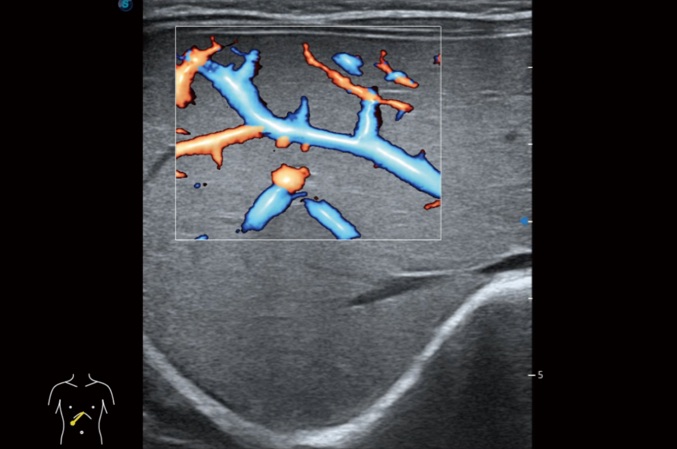

• SR Flow 高分辨率血流成像技术

高分辨率血流成像技术提高了对低速血流信号的检测能力。在提高空间分辨率的同时,也克服了血流外溢现象,为用户提供更加真实的血流动力学信息。